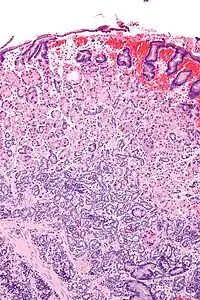

| Micrograph of a neuroendocrine tumour of the stomach. H&E stain. | |